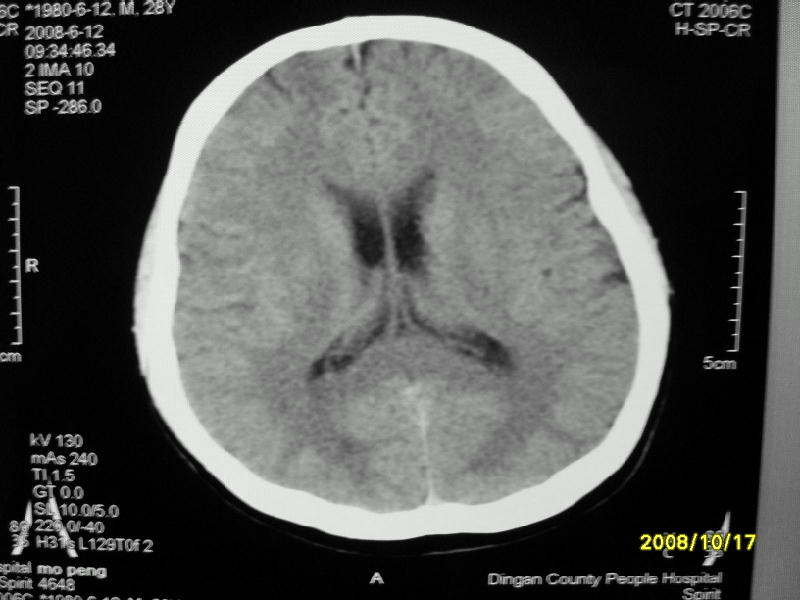

检查名称:     ct颅脑平扫           男     28岁

表现:左顶叶见斑点状致密影。边缘清,大小约0。3*1。0cm,余脑实质密度及灰白质结构示见异常。脑室系统大小,形态,密度未见异常。脑沟。脑裂。脑池未见异常密度影。中线结构无移位。

印象:左顶叶少许钙化灶

左顶叶见斑点状致密影。边缘清,大小约0。3*1。0cm,余脑实质密度及灰白质结构示见异常。脑室系统大小,形态,密度未见异常。脑沟。脑裂。脑池未见异常密度影。中线结构无移位。

印象:左顶叶少许钙化灶。